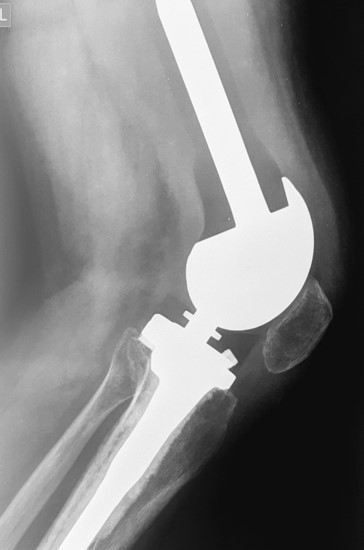

2. Остеосаркома большеберцовой кости

После получения предоперационной химиотерапии в МЦ ''Наири" была проведена органосохраняющая операции – сегментарная резекция верхней трети большеберцовой кости и коленного сустава, замещение образовавшегося костно-суставного дефекта индивидуальным, изготовленным на заказ эндопротезом. В послеоперационном периоде пациент продолжил показанную по протоколам химиотерапию. В настоящее время лечение завершено, признаков прогрессирования заболевания нет, оперированная конечность функционально пригодная, опороспособность полная.

После операции